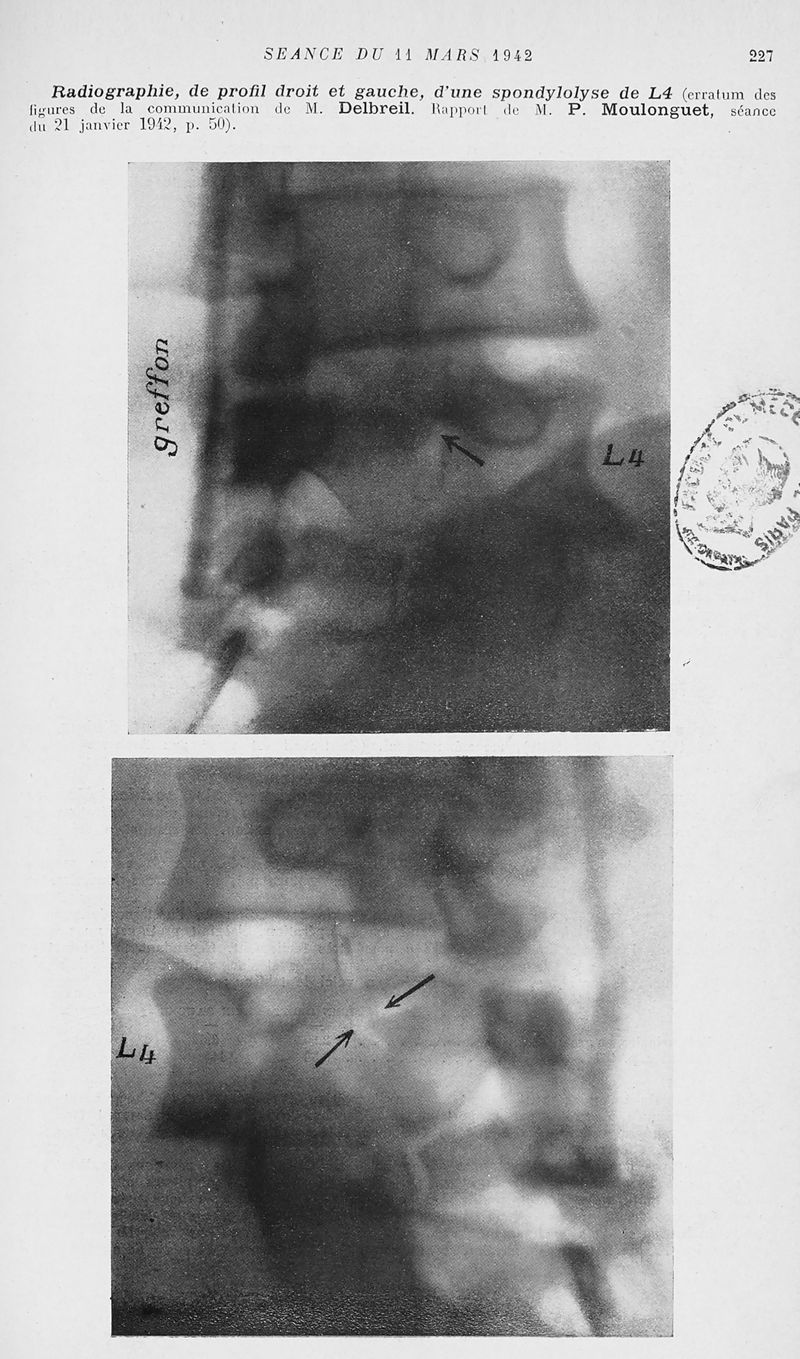

Mémoires de l'académie de chirurgie

Tome 68, 1942. - Paris : Masson, 1942.